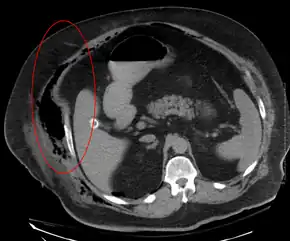

Imaging has a limited role in the diagnosis of necrotizing fasciitis. The time delay in performing imaging is a major concern. Plain radiography may show subcutaneous emphysema (gas in the subcutaneous tissue), which is strongly suggestive of necrotizing changes, but it is not sensitive enough to detect all the cases, because necrotizing skin infections caused by bacteria other than clostridial infections usually do not show subcutaneous emphysema. If the diagnosis is still in doubt, computed tomography (CT) scans and magnetic resonance imaging (MRI) are more sensitive modalities than plain radiography. However, both the CT scan and MRI are not sensitive enough to rule out necrotizing changes completely.[2] CT scan may show fascial thickening, edema, subcutaneous gas, and abscess formation.[2] In MRI, when fluid collection with deep fascia involvement occurs, thickening or enhancement with contrast injection, necrotizing fasciitis should be strongly suspected. Meanwhile, ultrasonography can show superficial abscess formation, but is not sensitive enough to diagnose necrotizing fasciitis.[2] CT scan is able to detect about 80% of cases, while MRI may pick up slightly more.[18]